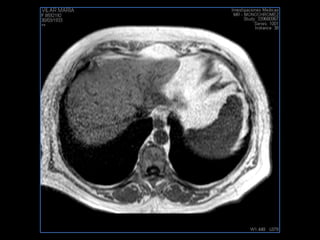

PROTOCOLO hígado graso AXIAL in phase y out phase AX T1 y AX fat sat +SAG T2  CON   GADOLINIO :  COR T1+AX T1(DIN) SAT: NO  FASE: RL THK: 4MM  COIL:  GAP: (FACTOR 1.4)  FOV: 40 CM NEX:2 SINCRONIZACION RESPIRATORIA EN 3 O 4 CICLOS ALE

PROTOCOLO hemocromatosis AXIAL supresión grasa /AX multieco en higado COR T2 AX T1 +SAG T2  CON   GADOLINIO :  COR T1+AX T1 SAT: NO  FASE: RL THK: 4MM  COIL:  GAP: (FACTOR 1.4) 1MM FOV: 40 CM NEX:2 SINCRONIZACION RESPIRATORIA EN 3 O 4 CICLOS ALE